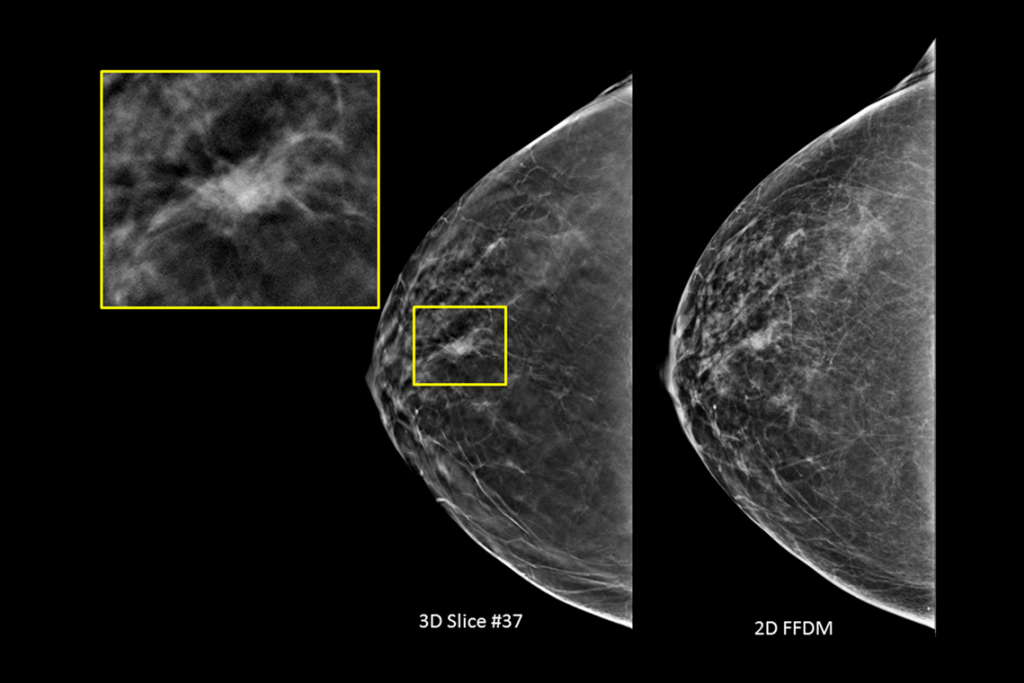

Imágenes clínicas de una mamografía

Imágenes clínicas de una mamografía de una mama grasa